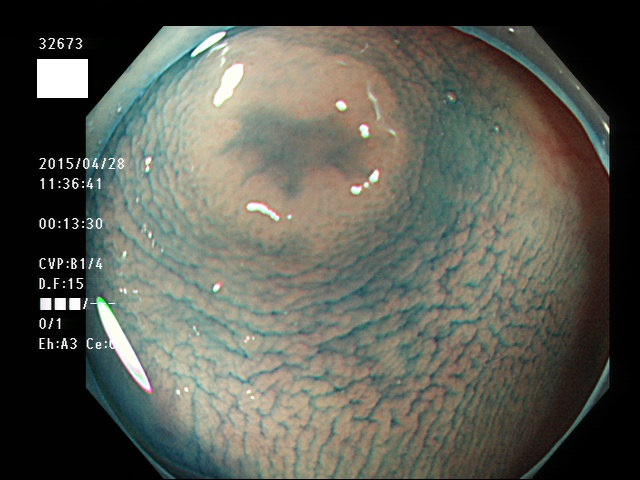

上記100名より抽出した平坦・陥凹型腺腫(=癌化の危険が高いが見落としやすい病変)の内視鏡写真